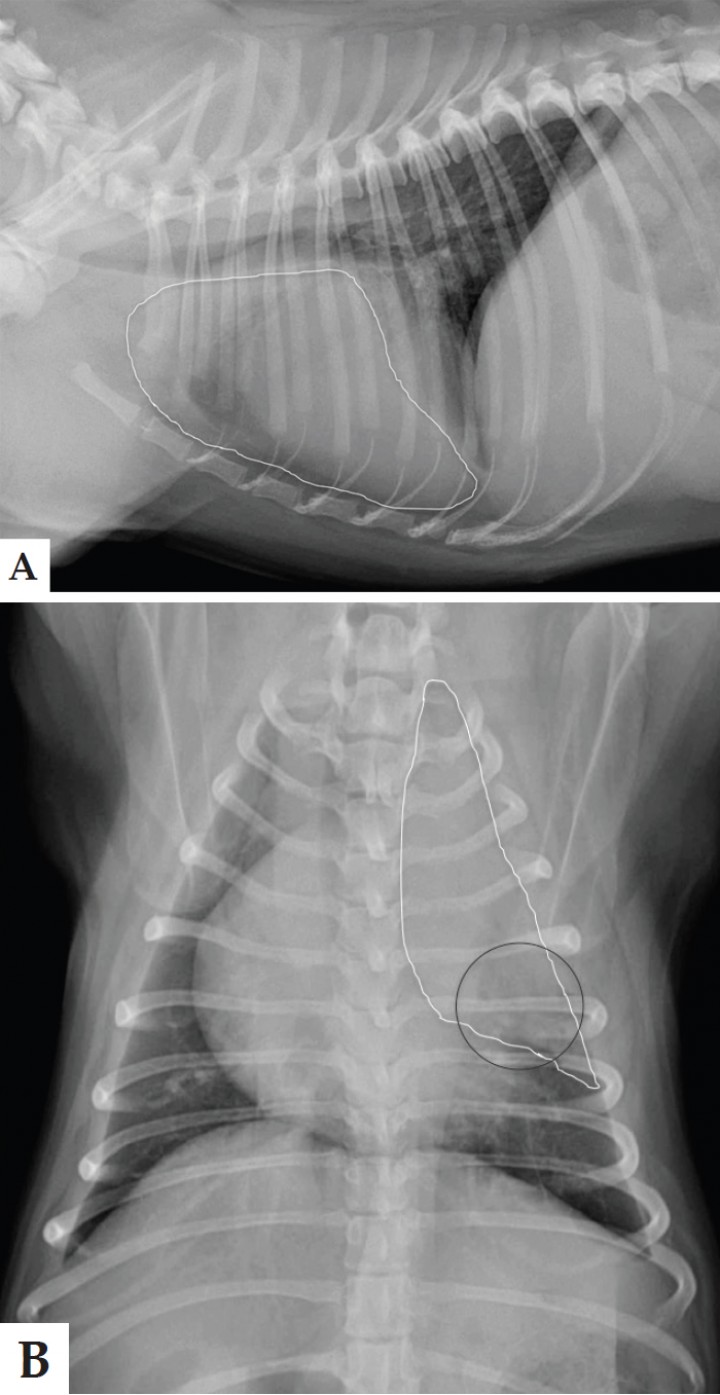

Perro macho de raza Carlino de 3 años de edad con un cuadro de decaimiento y tos de un mes de evolución. Durante el examen físico se detecta disminución de los sonidos pulmonares en el hemitórax izquierdo. La analítica sanguínea revela leucocitosis (42 x 103/µL; valor de referencia 6,0-17,0x 103/µL). Se realizan radiografías de tórax en proyecciones lateral derecha y ventrodorsal (Fig. 1).

<p>Radiografías de tórax en proyección lateral derecha (A) y ventrodorsal (B) de un Carlino de 3 años de edad, con un cuadro de decaimiento y tos de un mes de evolución.</p>

Radiografías de tórax en proyección lateral derecha (A) y ventrodorsal (B) de un Carlino de 3 años de edad, con un cuadro de decaimiento y tos de un mes de evolución.

Se observa un aumento de la opacidad pulmonar del lóbulo craneal izquierdo, representado por consolidación en la zona craneal y por un patrón alveolar en la zona caudal, sin desplazamiento de estructuras mediastínicas (Fig. 2). El resto de estructuras intra y extratorácicas no muestran alteraciones radiológicas significativas.

<p>Mismas imágenes que la Figura 1. Se observa un aumento de opacidad pulmonar, consolidación en área craneal y patrón alveolar en área caudal del lóbulo craneal izquierdo (área delimitada en blanco), sin desplazamiento de estructuras mediastínicas. El área círculo negro señala los broncogramas aéreos.</p>

Mismas imágenes que la Figura 1. Se observa un aumento de opacidad pulmonar, consolidación en área craneal y patrón alveolar en área caudal del lóbulo craneal izquierdo (área delimitada en blanco), sin desplazamiento de estructuras mediastínicas. El área círculo negro señala los broncogramas aéreos.